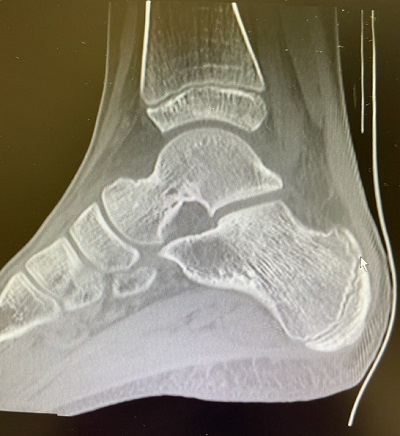

Durante 5 meses el paciente acude periódicamente a la consulta de pediatría de AP solicitando analgesia por dolor, destacando su facies triste y astenia. Ante esta evolución, desde AP se contacta con traumatología para realizar una resonancia magnética nuclear (RMN) de tobillo en la que se encuentran hallazgos sugestivos de osteoma osteoide subperióstico en cuello de astrágalo derecho, con nidus parcialmente mineralizado (Figuras 1 y 2). Se trata mediante ablación con radiofrecuencia, con adecuada respuesta y desaparición del dolor.

Figura 1. RM: tobillo con hallazgos sugestivos de osteoma osteoide subperióstien cuello de astrágalo derecho, con nidus parcialmente mineralizado